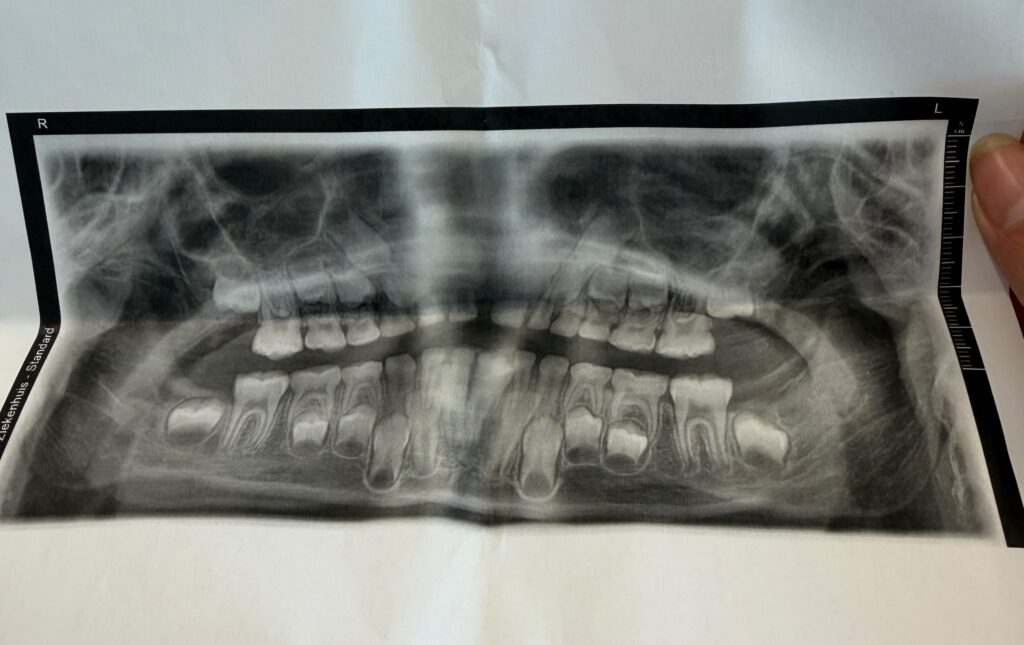

Home » Kleefstra » Kleefstra syndroom en het gebit, van de eerste tandjes tot ontbrekende volwassen tanden Kleefstra syndroom en het gebit, van de eerste tandjes tot ontbrekende volwassen tanden maart 4, 2026 Hoe het Kleefstra syndroom invloed kan hebben op het gebit Het Kleefstra-syndroom is een zeldzame genetische aandoening die invloed heeft op verschillende onderdelen van de ontwikkeling. Maar wist je dat ook het gebit zich vaak anders ontwikkelt dan bij een normaal kind? Dat kan al beginnen bij de eerste tandjes. Sommige kinderen met het Kleefstra syndroom krijgen hun tanden later dan gemiddeld. Noor was ruim een jaar toen haar eerste tandje doorbrak. Soms leek het gebit lange tijd stil te staan en kwamen er ineens meerdere tanden tegelijk door. Naast het moment waarop tanden doorkomen, kunnen ook de vorm en stand van tanden anders zijn. Sommige tanden zijn kleiner dan gemiddeld, iets ronder van vorm of staan wat verder uit elkaar. Bij een lach valt dan bijvoorbeeld op dat er meer ruimte tussen de voortanden zit. Het maakt een Kleefstra lach wel een herkenbaar en typisch lachje. Kenmerken die tandartsen vaker zien Bij kinderen en volwassenen met het Kleefstra syndroom beschrijven tandartsen een aantal kenmerken die relatief vaak voorkomen. Eén daarvan is een groter ruimte tussen tanden. Dat kan ontstaan doordat tanden wat kleiner zijn of doordat de kaakvorm anders ontwikkeld is.nOok een hoog gehemelte komt regelmatig voor. Dat betekent dat het gehemelte in de mond wat hoger en smaller is dan gemiddeld. Daardoor kan de tandboog ook smaller zijn, wat invloed heeft op hoe tanden doorbreken en hoe ze uiteindelijk in de kaak staan. Daarnaast kan de stand van tanden iets anders zijn. Sommige tanden groeien scheef of draaien een beetje. Soms sluiten de boven en ondertanden ook niet helemaal netjes op elkaar aan. Noor lijkt soort van schuine voortandjes te hebben. Een andere factor die invloed kan hebben op het gebit is de lagere spierspanning die bij het syndroom voorkomt. De spieren rond de mond werken dan anders, wat invloed kan hebben op kauwen, slikken en de ontwikkeling van de kaak. Help, mijn kind heeft kaasmolaren! Wanneer volwassen tanden ontbreken Bij sommige mensen met het Kleefstra syndroom gebeurt er nog iets anders met het gebit. Eén of meerdere blijvende tanden blijken nooit te zijn aangelegd. Tandartsen noemen dit hypodontie. Dat betekent dat de tand al tijdens de vroege ontwikkeling niet is gevormd. In de kaak ontstaan normaal kleine structuren die tandkiemen worden genoemd. Uit zo’n tandkiem groeit later een tand. Wanneer zo’n tandkiem niet ontstaat, kan de tand later ook niet doorkomen. Vaak wordt dit pas ontdekt wanneer een tandarts een röntgenfoto maakt om te kijken hoe het volwassen gebit zich ontwikkelt. Soms valt het eerder op doordat een melktand opvallend lang blijft zitten of doordat er een lege plek ontstaat waar eigenlijk een tand had moeten komen. Nu Noor de leeftijd van 8 jaar bereikt had, was het een mooi moment op haar gebit op de foto te zetten. En met veel trots kan ik zeggen dat al haar tanden aanwezig zijn! Omdat het Kleefstra syndroom zich bij iedereen anders uit, kijken tandartsen meestal heel individueel naar het gebit. Het belangrijkste is dat iemand goed kan eten, praten en zijn mond gezond kan houden. Het uiterlijk van het gebit is daarbij vaak minder belangrijk dan hoe goed het in het dagelijks leven functioneert. Gelukkig lijkt onze smikkelbeer nergens last van te hebben. Gerelateerde posts: WLZ aanvragen? Bureaucratie ten top! Twee opmerkelijke eerste reacties na de diagnose van Noor De WLZ aanvraag: eindelijk een besluit Papierwerk in het kwadraat